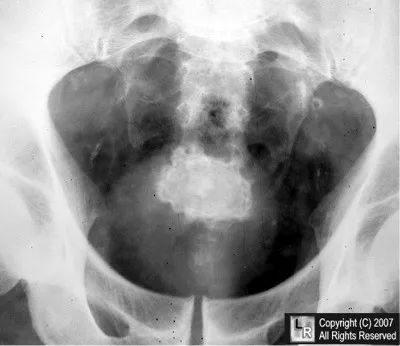

图1 患者下腹部X光片

参考答案:膀胱结石

膀胱结石是在空腔脏器(膀胱)中形成的,通常会有层状钙化,由严重钙化和基质材料的交替层组成。

膀胱结石首选常规的KUB(肾脏、输尿管和膀胱)X光片检查。在X光片上,尿酸和尿酸铵结石不透明。结石边缘呈锯齿状,类似“Jacks”游戏中的棋子,所以也称作“Jackstone结石”。